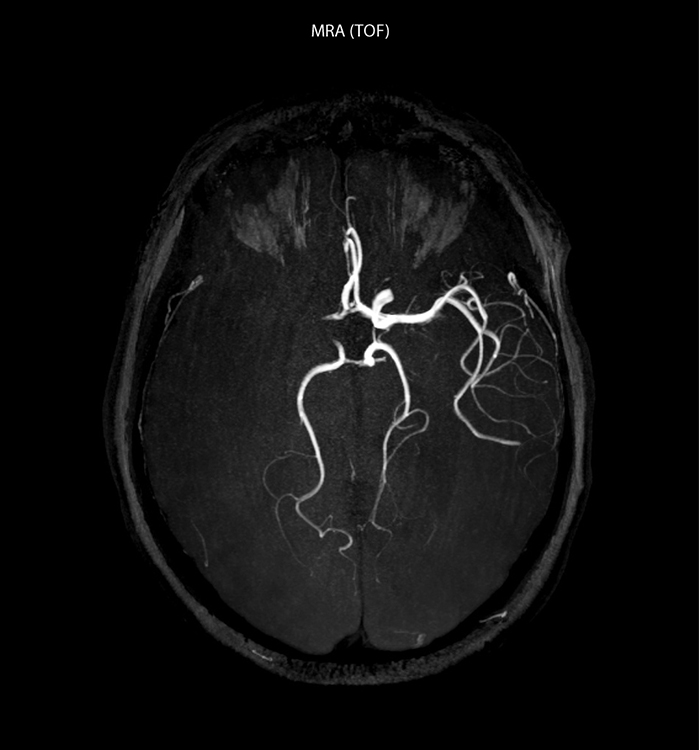

“Ingenia provides great flexibility in the parameters setting. We can tune a sequence the way we want,” says Dr. Savatovsky. “For example, in a stroke exam we use a FLAIR sequence of about two minutes instead of the four-minute FLAIR we use for MS. The diffusion is 30 seconds, the T2*-weighted scan is 30 seconds, the angiography scan time is less than one minute. Ingenia is a great scanner in that situation; even with these fast sequences we can achieve good images with good SNR. When the first sequence tells us that it’s not an ischemic stroke but a hemorrhagic stroke, we may switch to a time-resolved angiography to look for vascular malformations and venous thrombosis.

“Every center is different, but for me the ideal protocol for stroke includes diffusion weighted imaging, FLAIR, and fast susceptibility imaging,” says Dr. Savatovsky. “Our fast susceptibility weighted imaging takes 50 seconds, so it’s as fast as T2*-weighted imaging. It visualizes hemorrhage but also the clots. We also do 3D MR angiography that provides information on cervical and brain vessels. If the patient does not need immediate treatment, or if additional information is needed to decide on treatment, we might also add perfusion imaging and post-contrast T1-weighted imaging.”